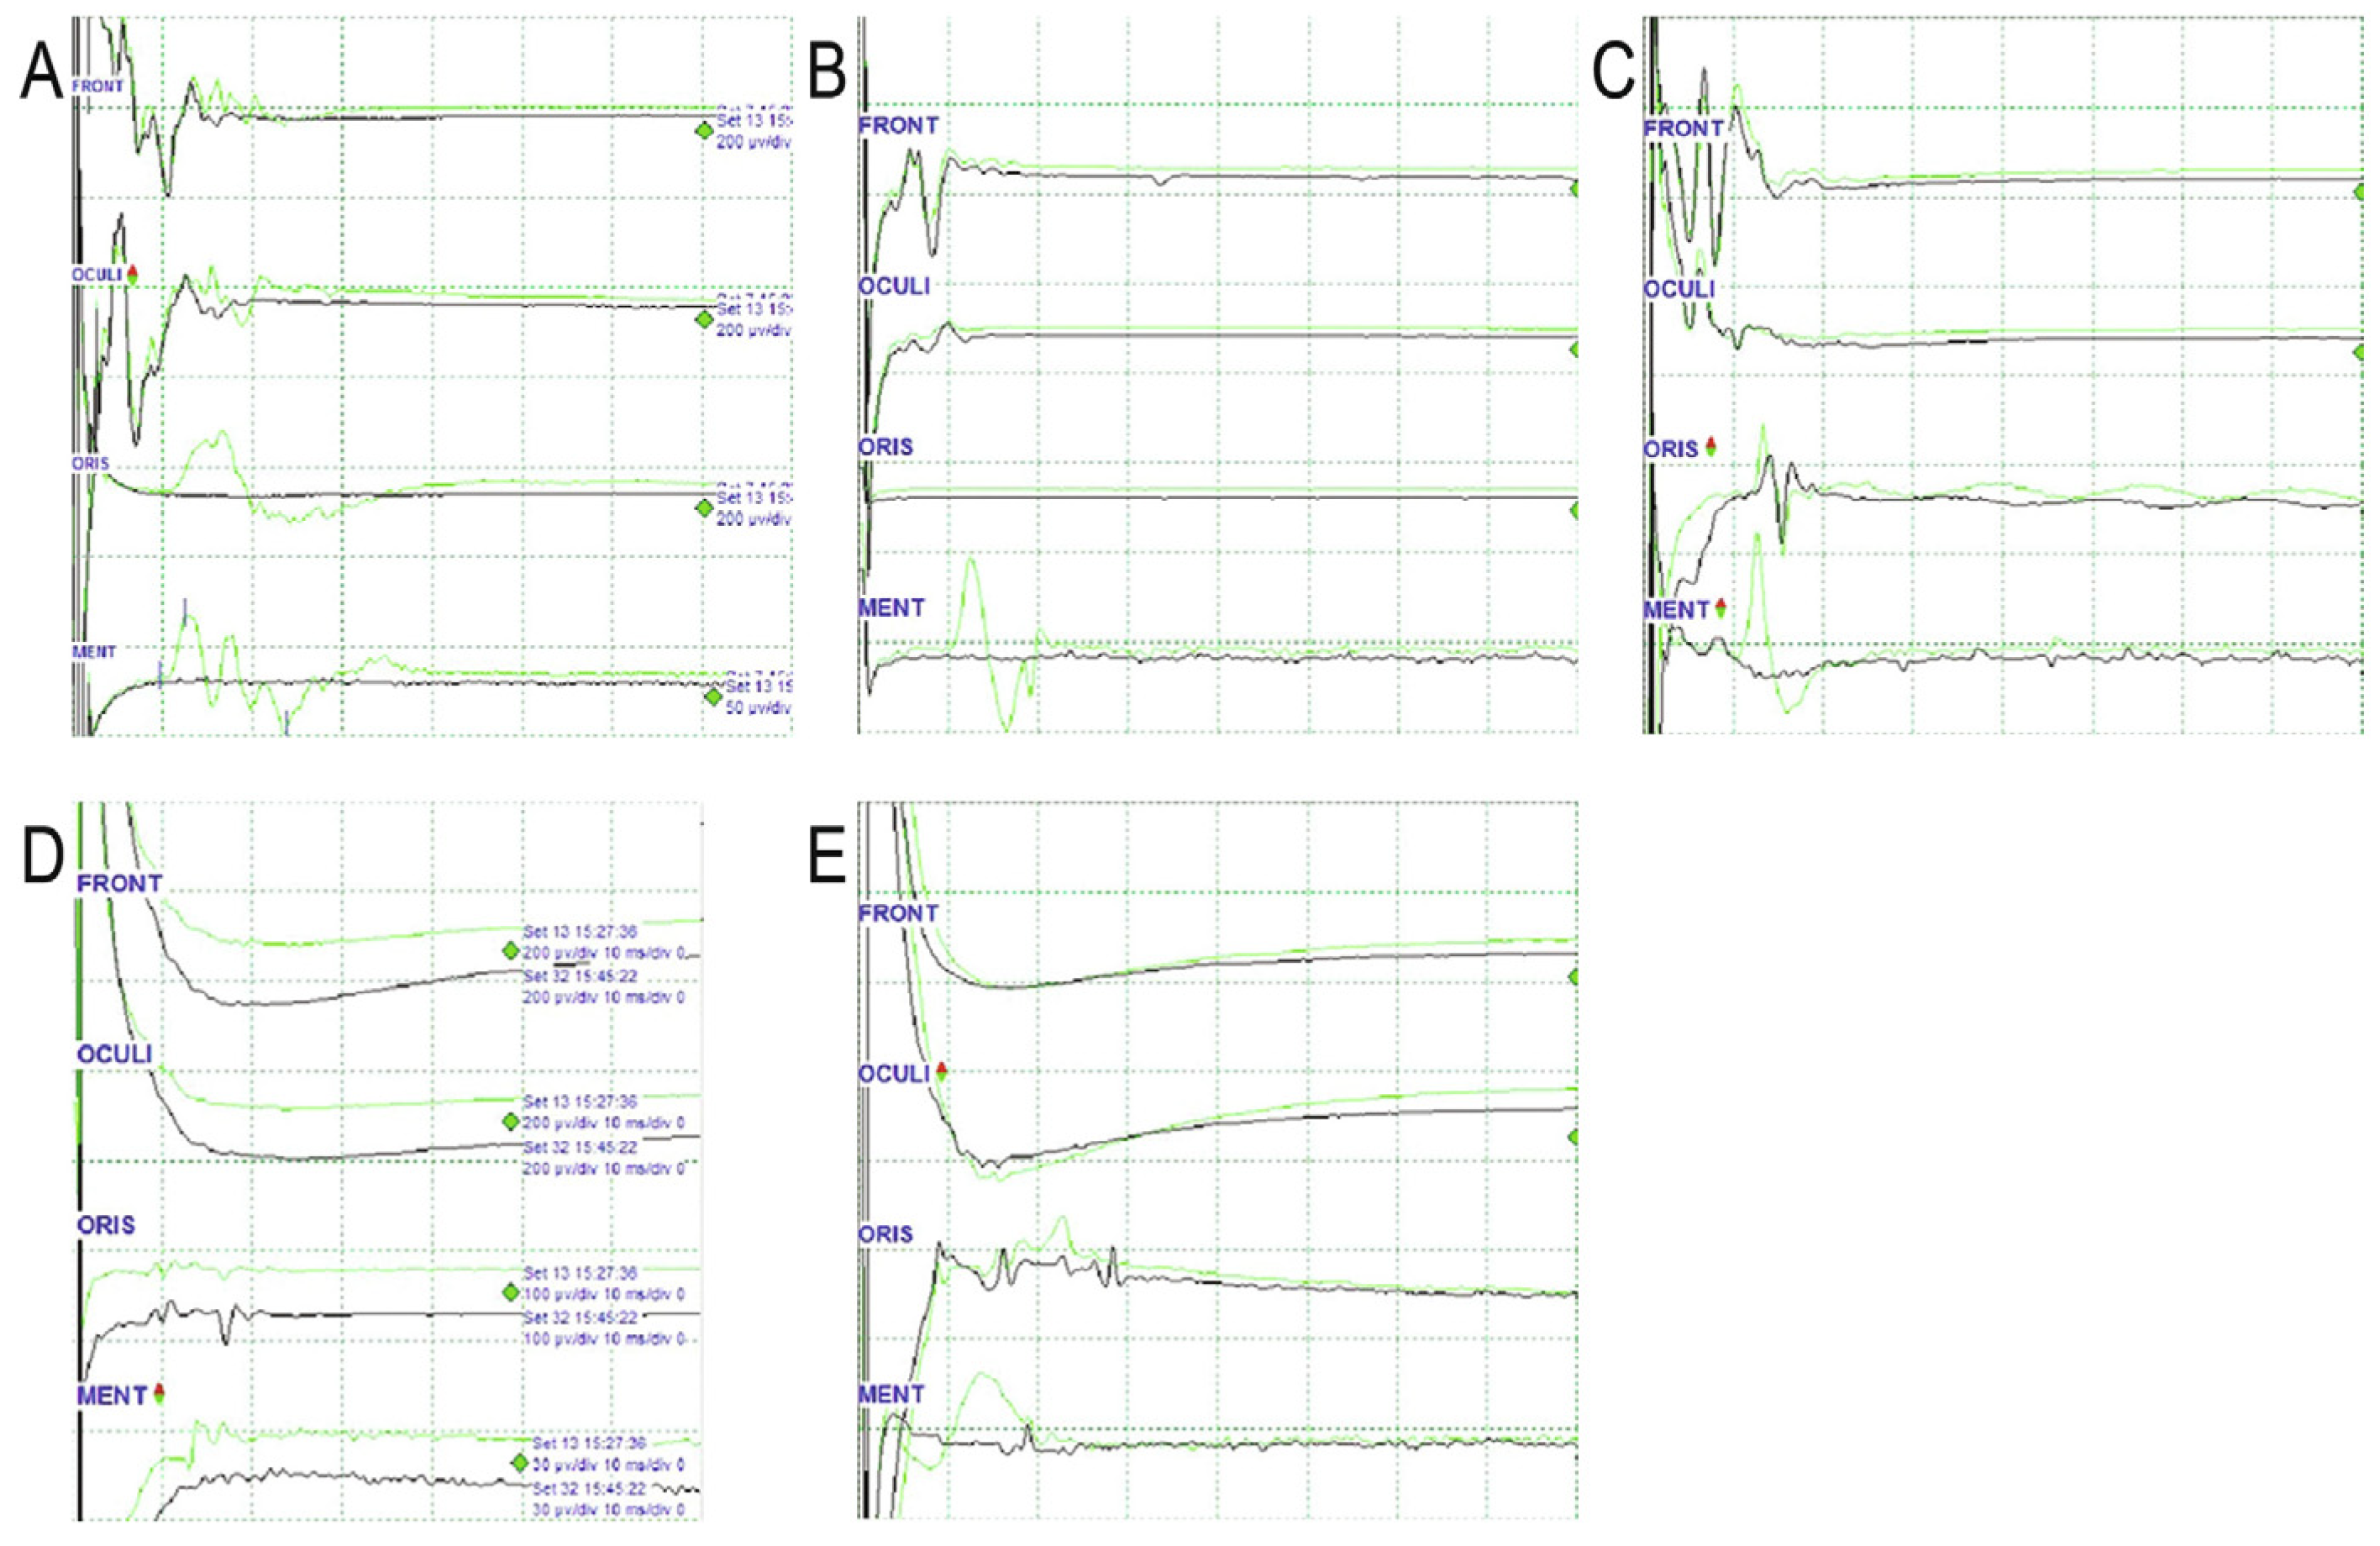

7. Revised Monitoring Protocol for the LSR (Figure 2)

8. Confirmation of a Positive LSR

9. Confirmation of LSR Disappearance